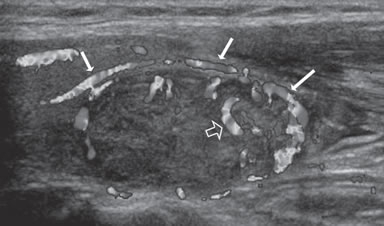

Figura 12. Nódulo coloideo, patrón de vascularización de predominio

periférico (flechas), con algunos vasos que se descuelgan hacia

el centro (flecha abierta).

Según la distribución de los vasos sanguíneos, los nódulos tiroideos se describen como hipovasculares (Figura 11), isovasculares (los menos frecuentes) e hipervasculares. En los hipervascularizados, se describen dos patrones. Un patrón de vascularización periférica (Figura 12) tiende a ser una característica de lesiones benignas (80-95% de nódulos hiperplásticos y adenomatosos) y un patrón de vascularización central o interna (Figura 13a), con o sin un componente periférico (Figura 13b) se observa en 70%- 90% de los nódulos malignos, aunque hay una considerable sobreposición, por lo que el optimismo inicial de que el “Doppler color” podía diferenciar nódulos benignos de malignos (Figura 13c) se ha ido esfumando gradualmente a medida que han ido apareciendo estudios con mayor número de pacientes18. Es necesario precisar que la mayoría de los nódulos hipervasculares son benignos, debido a que los nódulos hiperplásticos son mucho más frecuentes que los nódulos malignos (Figura 13d). El flujo vascular exclusivamente periférico en un nódulo bien delimitado, es frecuente de observar en nódulos hiperplásticos, y se le ha denominado el signo del “anillo de fuego” al “Doppler color”. Cerca de un 20% de los carcinomas papilares pueden ser hipovasculares (Figura 14a). Un nódulo avascular raramente corresponde a un tumor maligno (Figura 14b).